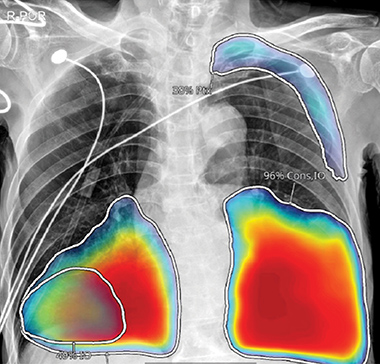

AI Diagnostic Assistance